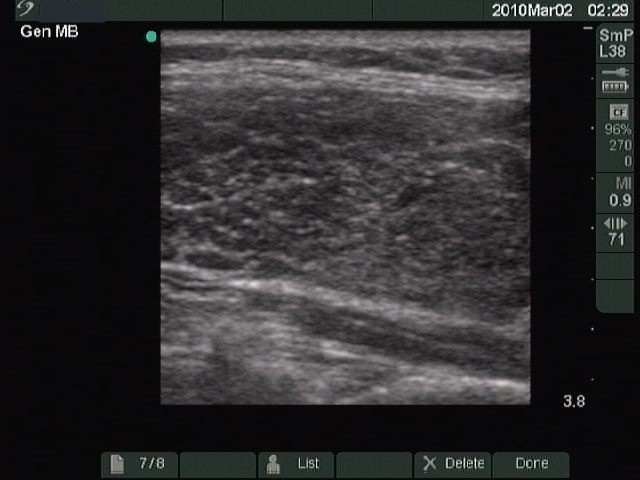

Ultrasonography: revealed a hypoechogenic thyroid with a large echonormal nodule in the left lobe.